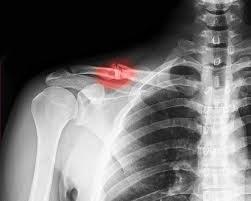

Xương đòn là một trong những xương chính ở vai, nối với xương bả vai với xương ức. Loại gãy xương này chiếm 5% trong tổng số ca gãy xương ở người trưởng thành. Hầu hết gãy xương đòn xảy ra khi ngã đập vai hoặc duỗi thẳng cánh tay gây đủ áp lực lên xương khiến xương bị gãy hoặc gãy. Xương đòn bị gãy có thể rất đau và khiến bạn khó cử động cánh tay.